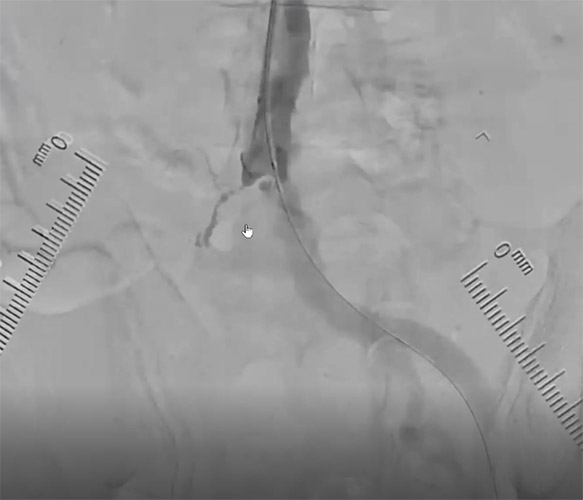

まずはエコーガイド下にPTAの穿刺を試みるが非常にシビアな石灰化に阻まれ穿刺不可となった。PTAの穿刺は諦め、開存しているATAを穿刺しZizai130cmガイド下に0.014inch 1gガイドワイヤーを使用しワイヤリングを実施。ATA入口部付近でZizaiから先端造影を実施。PTAが途中から閉塞していることを確認。【図4】ATAからPTAへワイヤーを反転させて、ワイヤーに追従させる形でZizaiを持ち込んだところ、先端部の柔軟性が高いことからワイヤーへスムーズにZizaiが追従出来たと考える。

ATAからそのままSFAへアプローチすれば手技が早くなる可能性があるが、万が一にでも開存している血管が詰まってしまうことを考慮し、TAIのルールとして血管性状が悪い方からアプロ―チすることが重要である。